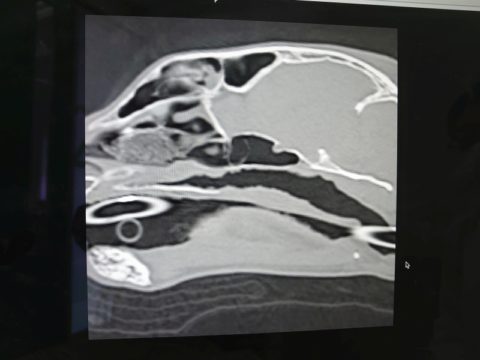

先生からCTと内視鏡の映像を見せてもらった

鼻咽頭内にぼこぼこしたものがへばりついてる..

確かに先日見せてもらったワンちゃんの狭窄とは異なり、空洞は広いようだけど何かがへばりついてる..

先生が言っていた「ぼこぼこしたもの」は、この白いぼこぼこのことだった

鼻咽頭内は膿とか血液とか鼻汁とかはなく、ただぼこぼこしたものが覆い尽くしている..

先生の所見では今のところこれが炎症によるものなのか、リンパ腫なのかは判断できないとのこと..